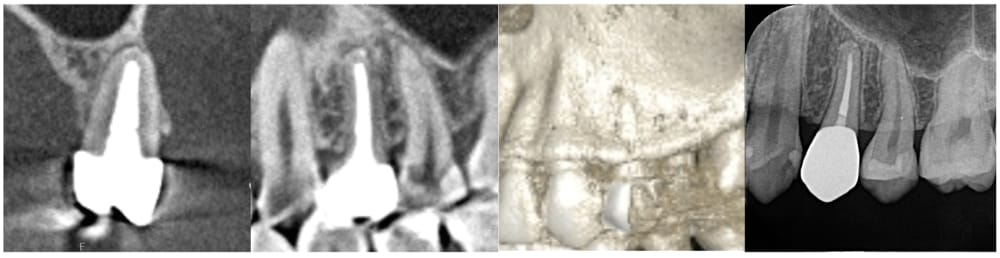

左上の第一小臼歯(4番)には虫歯が認められ、レントゲン・CTにて明瞭な骨吸収像が認められました。痛みなどの症状はないものの、このまま被せ物の治療をやりかえる場合、将来的に根の先の膿が大きくなる可能性があるため、根管治療が第一選択であるとお伝えし、根管治療を開始することになりました。

術後24ヶ月が経過時点でのCT画像では、もともとはっきりと写っていた根の先の黒い部分は完全に消失し、骨の回復が認められます。被せ物の適合にも問題なく、良好な経過をたどっています。